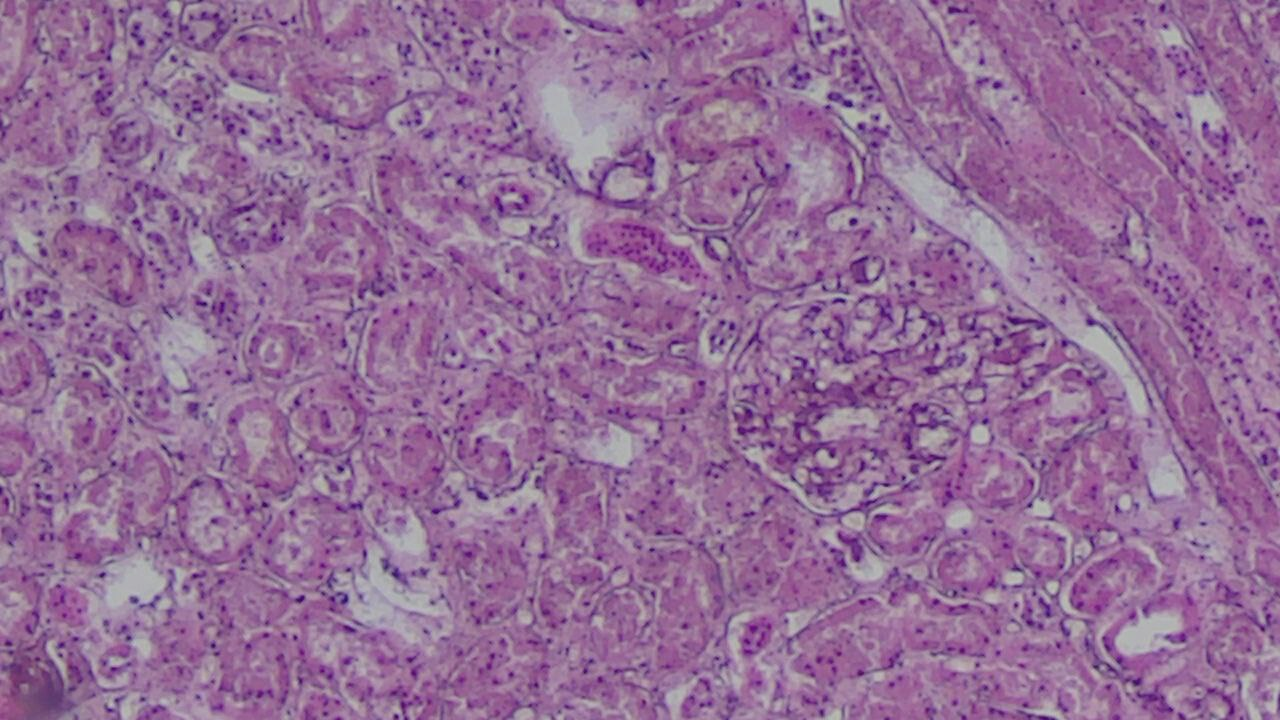

The architecture of the muscle fibers is disrupted. Cardiomyocytes in some areas are sharply eosinophilic, with a loss of normal transverse striation. Fragmentation and wavy deformation of muscle fibers are observed. The nuclei of cardiomyocytes are heterogeneous: some are hyperchromic and elongated, while others exhibit karyopyknosis, and in some places, karyolysis. Morphological Findings in Other Organs. Morphological examination of the corpses of individuals who died from acute oral poisoning revealed a complex of typical histological changes, indicating systemic toxic damage to the body and the development of severe hypoxic-metabolic disorders. Brain: In all observations, signs of pronounced cerebral edema, expansion of perivascular spaces, venous congestion, and focal perivascular hemorrhages were noted. These findings reflect impaired microcirculation and hypoxic damage to the nervous tissue. Liver: Dystrophic changes in hepatocytes predominated, with the development of fatty degeneration (steatosis) of varying degrees of severity. In the central zones of the hepatic lobules, areas of centrilobular necrosis were identified, indicating the high sensitivity of hepatocytes to toxic effects and ischemia. | Figure 2. Hepatocytes are predominantly enlarged, with pale, granular cytoplasm showing pronounced signs of acute toxic dystrophy. Stained with H&E, mag. 10x20 |

In a number of liver tissue cells, vacuolization of the cytoplasm is observed, in some areas progressing to hydropic dystrophy. The nuclei of hepatocytes are heterogeneous, with detectable karyopyknosis and focal karyolysis, indicating initial necrobiotic changes.Kidneys: Characteristic findings included pronounced dystrophic changes and necrosis of the epithelium of the convoluted tubules, accompanied by interstitial edema and vascular congestion. This corresponds to the morphological picture of acute toxic nephropathy and acute renal failure. The basement membranes of the tubules are generally preserved. The interstitial tissue is moderately edematous, and the microcirculatory vessels are sharply congested, occasionally showing signs of stasis. The lumina of the tubules are unevenly dilated and, in some places, filled with proteinaceous masses, which is consistent with the pattern of acute tubular necrosis. | Figure 3. Glomeruli are generally preserved in configuration; however, some exhibit congestion of the capillary loops, and in certain areas, their moderate collapse. The lumina of the tubules are unevenly dilated and partially filled with proteinaceous masses, consistent with the pattern of acute tubular necrosis. Stained with H&E, mag. 10x20 |